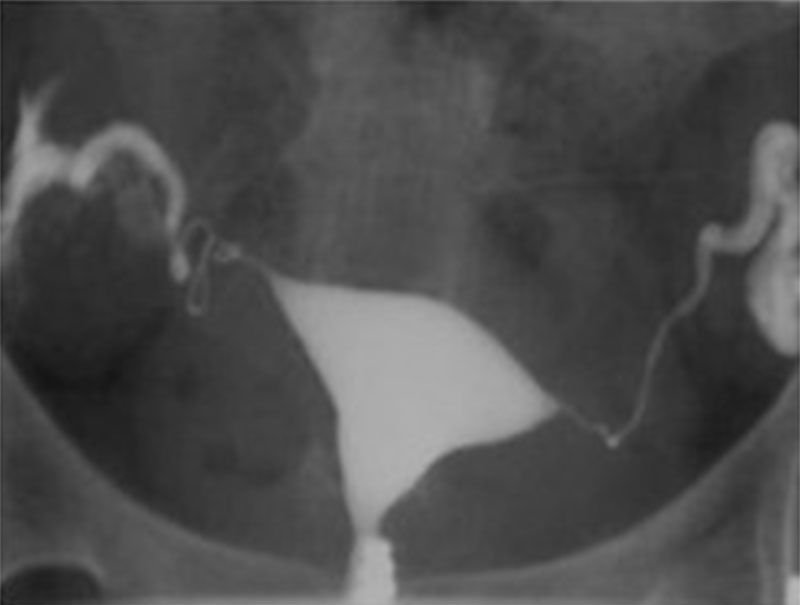

Αρχικά η γυναίκα καλείται να ξαπλώσει σε ένα ειδικό ακτινολογικό τραπέζι κάτω από ένα μηχάνημα ακτίνων Χ. Στη συνέχεια, τοποθετεί τα πόδια της σε στηρίγματα, σαν να επρόκειτο να ακολουθήσει τεστ Παπ. Ένα εργαλείο που ονομάζεται κολποδιαστολέας τοποθετείται στο άνοιγμα του κόλπου, με τη μικρότερη δυνατή ενόχληση. Αφού ο τράχηλος καθαριστεί και προετοιμαστεί κατάλληλα, στη συνέχεια ο εξειδικευμένος ακτινολόγος τοποθετεί ένα λεπτό και μαλακό σωλήνα (καθετήρα) στο στόμιο του τραχήλου. Στη συνέχεια, η σκιαγραφική ουσία ρέει μέσω αυτού του σωλήνα, “γεμίζοντας” με αυτόν το τρόπο τις κοιλότητες της μήτρας και των σαλπίγγων. Κατά το σύντομο αυτό χρονικό διάστημα που οι κοιλότητες “γεμίζουν” με το σκιαγραφικό υλικό (5-10 λεπτά) λαμβάνονται στοχευμένα ακτινογραφίες.

Ο ρόλος του ιωδιούχου υδατοδιαλυτού σκιαγραφικού υλικού, είναι να αποτυπώσει αυτές τις περιοχές (μήτρα και σάλπιγγες) με ακρίβεια στις ακτινογραφίες. Ορισμένες φορές, κατά τη διαδικασία της εξέτασης, η γυναίκα μπορεί να χρειαστεί να αλλάξει θέση προς το Αριστερό ή Δεξιό πλάγιο, προκειμένου να γίνουν καλύτερα κάποιες λήψεις. Συνήθως, ανάλογα βέβαια και με τα ευρήματα, η εξέταση ολοκληρώνεται με μια ακτινογραφία της ασθενούς σε όρθια θέση, προκειμένου να διαπιστωθεί πως το σκιαγραφικό υλικό έχει τελικά περάσει εξ’ολοκλήρου στη περιτοναϊκή κοιλότητα και δεν έχουμε κάποια κατακράτηση υγρού στις σάλπιγγες ( πχ σε περίπτωση συμφύσεων).